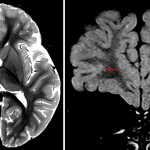

- T2/FLAIR hyperintense lesion in the juxtacortical white matter of the inferior right frontal lobe with likely adjacent cortical involvement

- The lesion has a somewhat multinodular appearance

- No corresponding enhancement, restricted diffusion, susceptibility artifact, or mass effect

Focal cortical dysplasia vs multinodular and vacuolating neuronal tumor (MVNT)